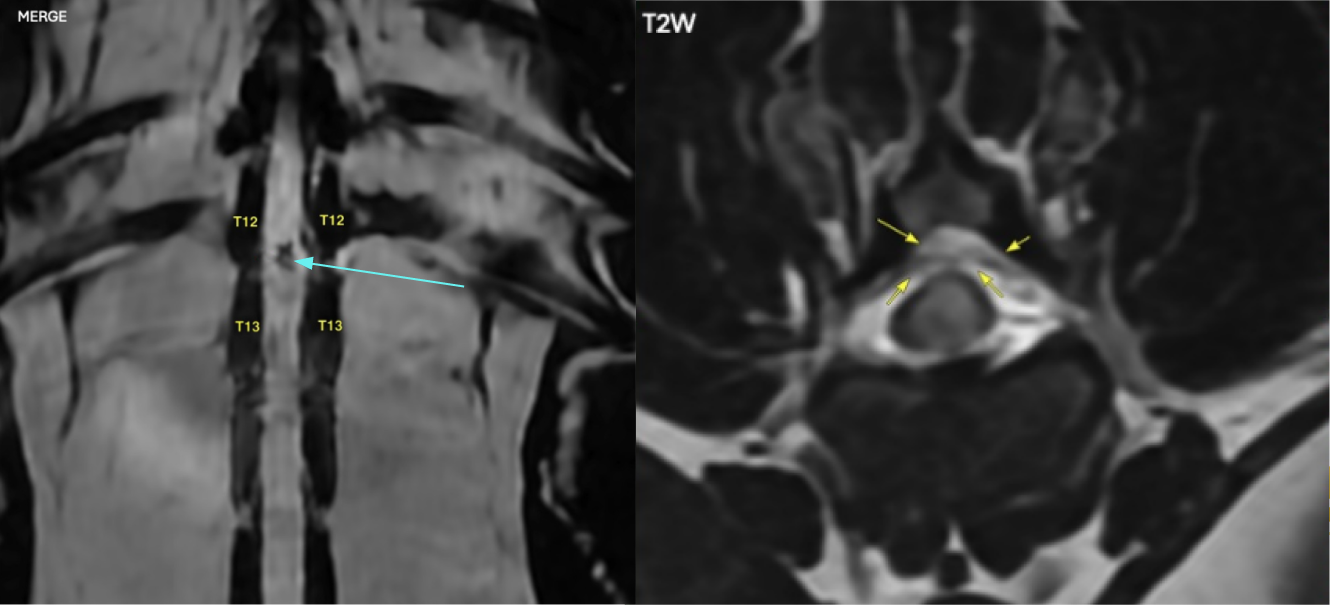

Kali’s back is illustrated on the left by an MRI image (A), revealing an intradural spinal cord defect (light blue arrow) that aligns with a small area of hemorrhage situated within the spinal cord. The image (B) on the right is a cross-section MRI at T12-3, which clearly shows a defect within the spinal cord representing the hemorrhage, swelling, and bruising from the tiny disk passing through the spinal cord. There is no compression from this ANNPE.

An emergency MRI revealed the cause immediately. Kali had an Acute Non-Compressive Nucleus Pulposus Extrusion (ANNPE) at T12-13 — otherwise known as a traumatic disk. ANNPE, or traumatic disk, is a condition where a tiny piece of normal, hydrated disk material 'explosively' ruptures into the spinal canal.

This small fragment violently passes through the spinal cord and disrupts the blood supply, causing severe neurological dysfunction. Critically, this is a vascular process — the disk material does not significantly compress the spinal cord — meaning that in most cases surgery isn’t necessary.